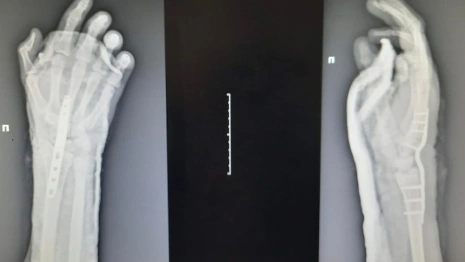

Подростка привезли в Университетскую клинику 1 марта из Коврова, в тот же день вечером врачи провели операцию по реимплантации конечности. Сейчас состояние пациента стабильное, кровоснабжение кисти удалось восстановить.